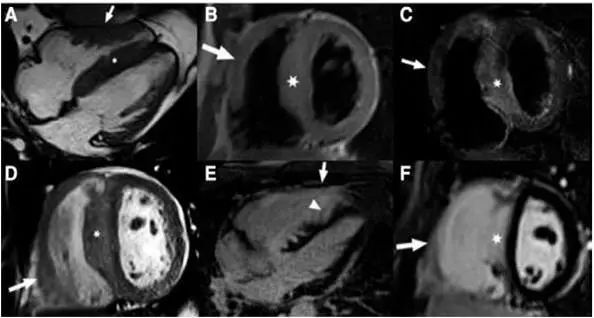

3.心脏磁共振成像

心脏磁共振成像较超声心动图提供的信息更多。钆对比剂延迟强化 (1ate gadolinium enhancement,LGE)是识别心肌纤维化最有效的方法,LGE与死亡、SCD等风险正相关。约65%的HCM患者出现LGE,多表现为肥厚心肌内局灶性或斑片状强化,以室间隔与右心室游离壁交界处局灶状强化最为典型。